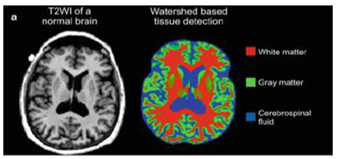

- Watershed line: it interprets an image as a height profile, flooded from regional minima so that, the lines where the flooded areas touch represent the watersheds [99,100]. It makes it possible to use the a priori knowledge of the clinician and his intervention, which facilitates visual evaluation in the higher level. However, it is difficult to implement and slow from a calculation point of view. In addition, the over-segmentation of images is generally frequent.